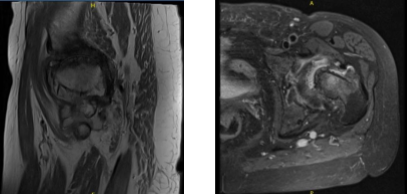

In left hip MRI, Bone and Joint there is severe joint space narrowing the left hip joint with bone-on-bone contact. There is subchondral bone marrow edema subchondral cyst in the lateral acetabulum and lateral aspect of the femoral head with bone marrow edema extending into the femoral neck and intertrochanteric fossa.

There is flattening of the femoral head. There is extensive full-thickness cartilage loss. There is a moderate left hip joint effusion with synovitis. There is diffuse tearing of the labrum. The Tendons/Muscles have visualized tensor fascia lata, rectus femoris, hamstring tendons and iliopsoas intact.

No iliopsoas bursitis is noted. The gluteus Medius and minimus insertions are intact. No trochanteric bursitis is noted. The ischiofemoral interspace and quadratus femoris muscles are intact.

The piriformis muscles and the common rectus abdominis, and adductor aponeurosis are intact. The visualized sciatic nerve is intact. There is marked scoliosis.

The nerves have a fat plane surrounding the sciatic nerve. In Pelvis and Contralateral Hip: The pubic symphysis is intact. There is marked osteoarthritis in the right hip joint. The visualized pelvic visceral structures appear normal. No enlarged lymphadenopathy. No free fluid in the pelvis.

The periarticular subcutaneous tissues are unremarkable. It has a severe osteoarthritis in the left hip joint with associated subchondral bone marrow edema in the femoral head and neck and flattening of the femoral head. Diffuse tearing labrum. Moderate left hip joint effusion.

MRI Left hip non-contrast